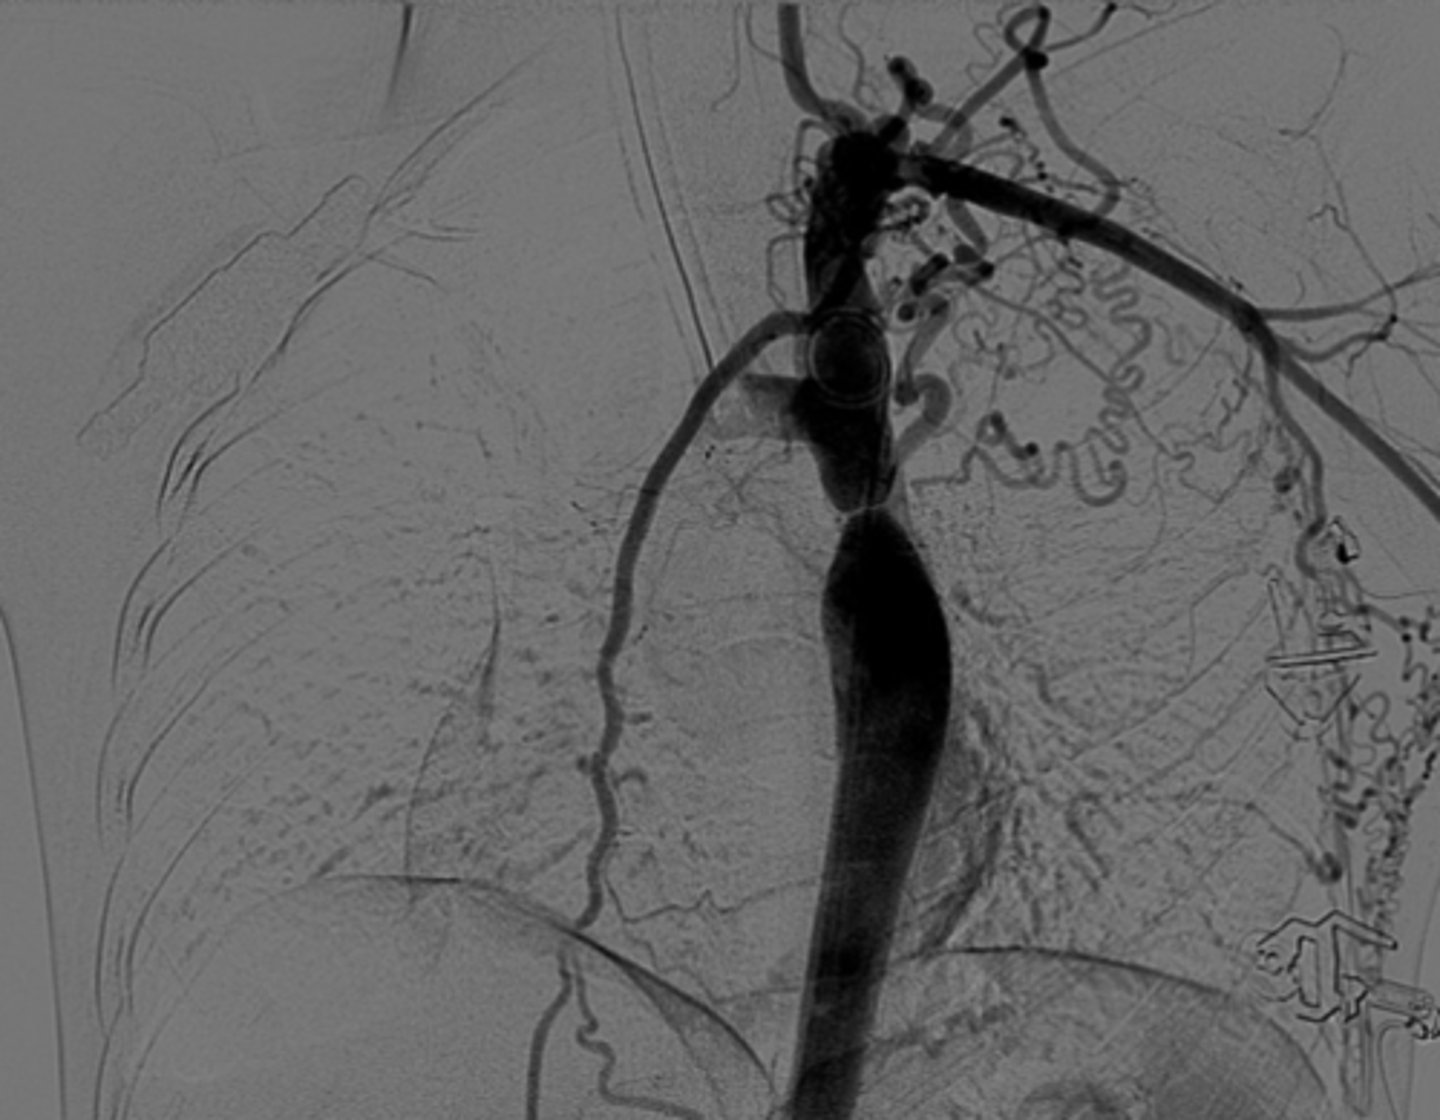

Know the development of the aortic arches figure

knowt flashcard image

What is the chest radiograph finding in coarctation of the aorta?

Figure 3 sign.

<p>Figure 3 sign.</p>

82

New cards

What causes dysphagia lusoria?

Abnormal origin of the right subclavian artery results in compression of the esophagus -impairment of swallowing

<p>Abnormal origin of the right subclavian artery results in compression of the esophagus -impairment of swallowing</p>

83

What is a double aortic arch?

Persistence of both right and left aortic arches forming a vascular ring.

<p>Persistence of both right and left aortic arches forming a vascular ring.</p>